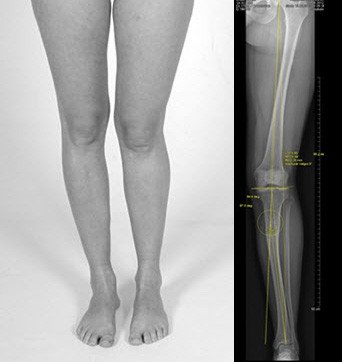

Knochenverlängerung am Unterschenkel und Korrektur von X-Beinen (Taylor Spatial Frame)

Vor der Operation

Es besteht eine sehr ungünstige posttraumatische X-Beinfehlstellung und Beinverkürzung am Unterschenkel auf der linken Seite. Bei Belassen dieser Fehlstellung droht ein frühzeitiger Verschleiss des Gelenkes aussenseitig.